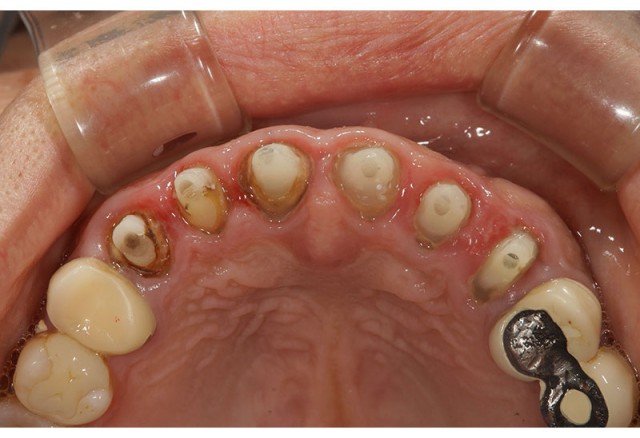

施術前

今回術前画像がないのですが、上の歯6本をオールセラミックで審美回復させていただきました。この患者さんは以前保険診療により被せ物をされていましたが、変色や黒ずみが気になりだしたとのことで今回の審美術による回復となりました。

画像のように新しいオールセラミックがしっかりとかぶさるように土台を形成していきます。